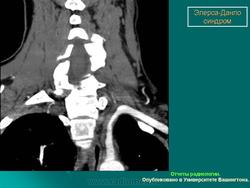

3. Васкулярный тип.

Наследуется по аутосомно-доминантному типу. Основные диагностические критерии: тонкая, прозрачная кожа, разрывы стенки артерий, кишечника и/или матки,обширные кровоизлияния, характерный фенотип. Дополнительные диагностические критерии: гипермобильность мелких суставов, разрыв сухожилий и мышц, косолапость, варикозное расширение вен с ранней манифестацией, артериовенозные каротидно-кавернозные фистулы, пневмоторакс/пневмогидроторакс, атрофия десневого края; положительный семейный анамнез, случаи внезапной смерти у близких родственников (многие пациенты не доживают до 50 лет из-за разрыва артерий или, что реже кишечника). Наличие двух и более главных критериев с большой вероятностью указывает на диагноз васкулярного типа СЭД и является показанием для лабораторной диагностики. Нередко отмечается характерный фенотип (узкий нос, тонкие губы, натянутая кожа, впавшие щеки и экзофтальм, обусловленный, в основном, снижением подкожно-жирового слоя). Надо отметить, что такой фенотип характерен для взрослых больных, а у детей он практически не выражен. Гипермобильность суставов обычно ограничена суставами пальцев. Максимальная частота спонтанных артериальных разрывов приходится на третью-четвертую декады жизни, но они могут возникать и раньше. Чаще всего вовлечены артерии среднего калибра. Беременность и роды могут осложняться разрывом матки и маточными кровотечениями, а также разрывом влагалища и промежности. Именно артериальные разрывы являются наиболее частой причиной внезапной смерти. Поэтому в качестве диагностических мероприятий рекомендуются, по возможности, неинвазивные процедуры. При этом типе СЭД сравнительно хорошо изучены изменения на молекулярно-белковом уровне. Этиологическим фактором являются мутации в гене коллагена IIIтипа.